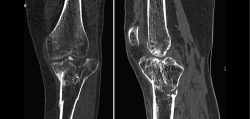

Tomografía axial computarizada

Es un método de diagnóstico médico que permite observar el interior del cuerpo humano, a través de cortes milimétricos transversales al eje cefalocaudal, mediante la utilización de los rayos X(9).

El principio básico de la TAC es que la estructura interna de un objeto puede reconstruirse a partir de múltiples proyecciones de ese objeto.

La imagen se adquiere combinando la rotación continua del tubo de rayos X con el desplazamiento lineal de la mesa de exploración.

Los equipos modernos (TAC helicoidal o multicorte) permiten obtener imágenes volumétricas isotrópicas, lo que significa que la reconstrucción multiplanar en cada uno de los ejes tiene la misma resolución. Además, permite hacer reconstrucciones tridimensionales.

Entre las ventajas de la TAC, cabe destacar que permite obtener imágenes de hasta 1 mm y que, debido a la amplia gama de tonos grises que maneja, permite identificar con precisión los diferentes tejidos estudiados.

Entre sus inconvenientes, hay que tener en cuenta que a veces es necesario el uso de contraste intravenoso y que utiliza radiaciones ionizantes.

1. Fracturas

Es esencialmente útil en la valoración de los trazos de fractura, de su extensión, del escalón intraarticular y el desplazamiento. También es importante en la planificación del tratamiento de las fracturas intraarticulares complejas.

Los nuevos equipos, con múltiples detectores, permiten realizar cortes finos (submilimétricos) y reconstrucciones en cualquier plano del espacio o tridimensionales (3D) de gran calidad, que facilitan la valoración de estas lesiones(7).

1.2. Tibia (Figura 20)

Figura 20. Corte de reconstrucción coronal de tomografía axial computarizada de rodilla: fractura de ambas mesetas tibiales.